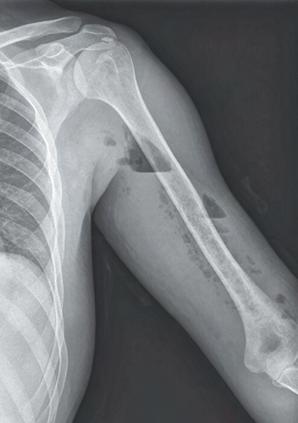

Recent studies indicate that Generative Pre-trained Transformer 4 with Vision (GPT-4V) outperforms human physicians in medical challenge tasks. However, these evaluations primarily focused on the accuracy of multi-choice questions alone. Our study extends the current scope by conducting a comprehensive analysis of GPT-4V's rationales of image comprehension, recall of medical knowledge, and step-by-step multimodal reasoning when solving New England Journal of Medicine (NEJM) Image Challenges - an imaging quiz designed to test the knowledge and diagnostic capabilities of medical professionals. Evaluation results confirmed that GPT-4V outperforms human physicians regarding multi-choice accuracy (88.0% vs. 77.0%, p=0.034). GPT-4V also performs well in cases where physicians incorrectly answer, with over 80% accuracy. However, we discovered that GPT-4V frequently presents flawed rationales in cases where it makes the correct final choices (27.3%), most prominent in image comprehension (21.6%). Regardless of GPT-4V's high accuracy in multi-choice questions, our findings emphasize the necessity for further in-depth evaluations of its rationales before integrating such models into clinical workflows.